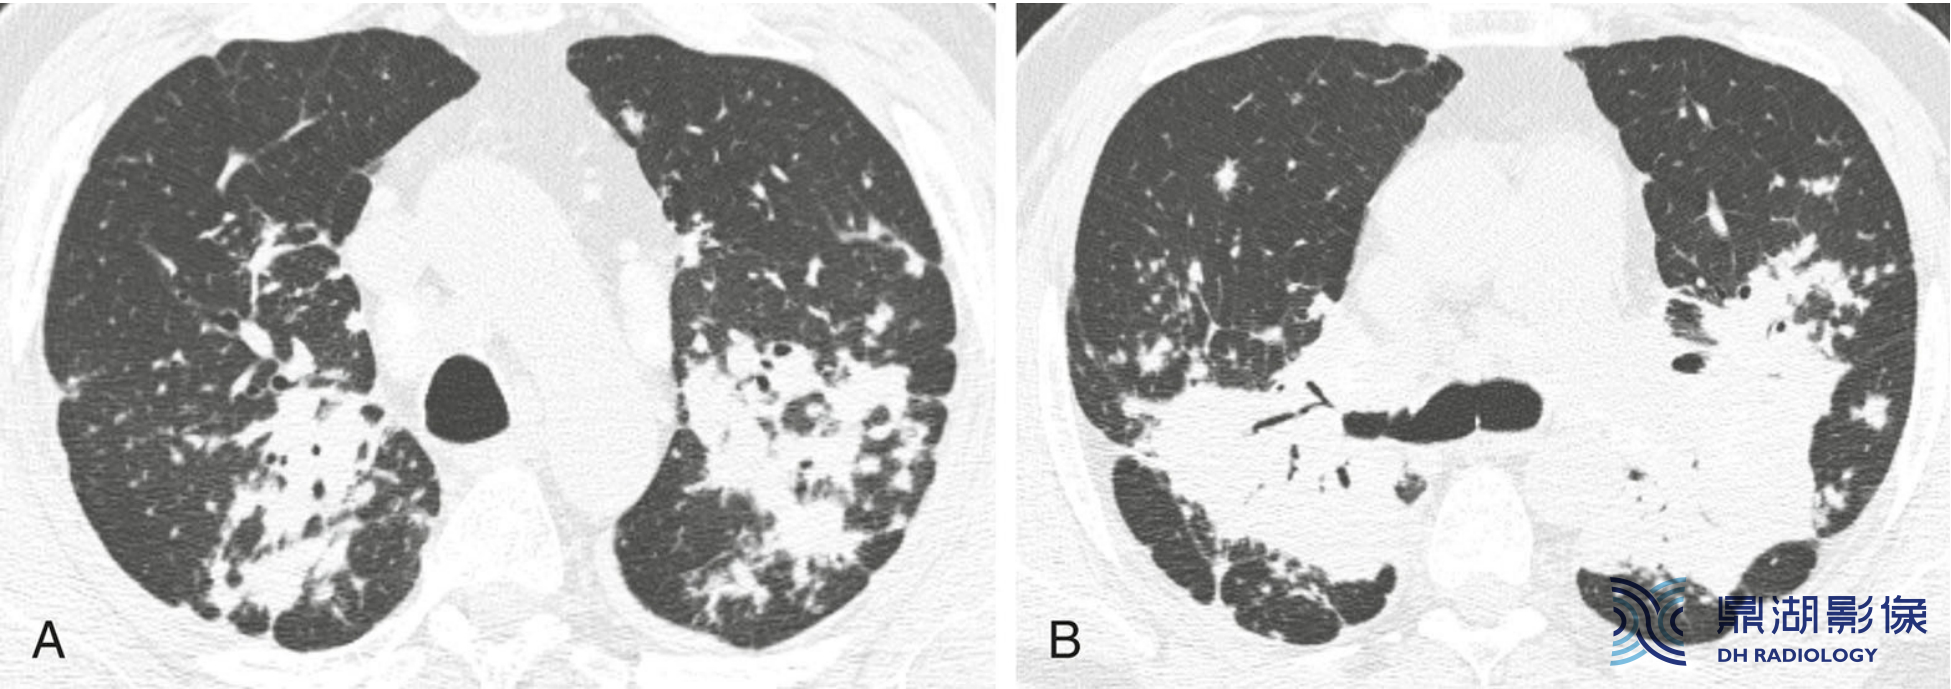

69000f6fce6484de7792f53840129a2e.png

结节病末期伴牵拉性支气管扩张和囊腔形成的典型表现。上肺(A)和中肺(B)图像显示未期结节病可见广泛分布于肺门旁和上叶的囊性病变。扩张的支气管与囊或肺气肿难以鉴别。足分枝菌病常见于伴有纤维化表现的结节病患者。